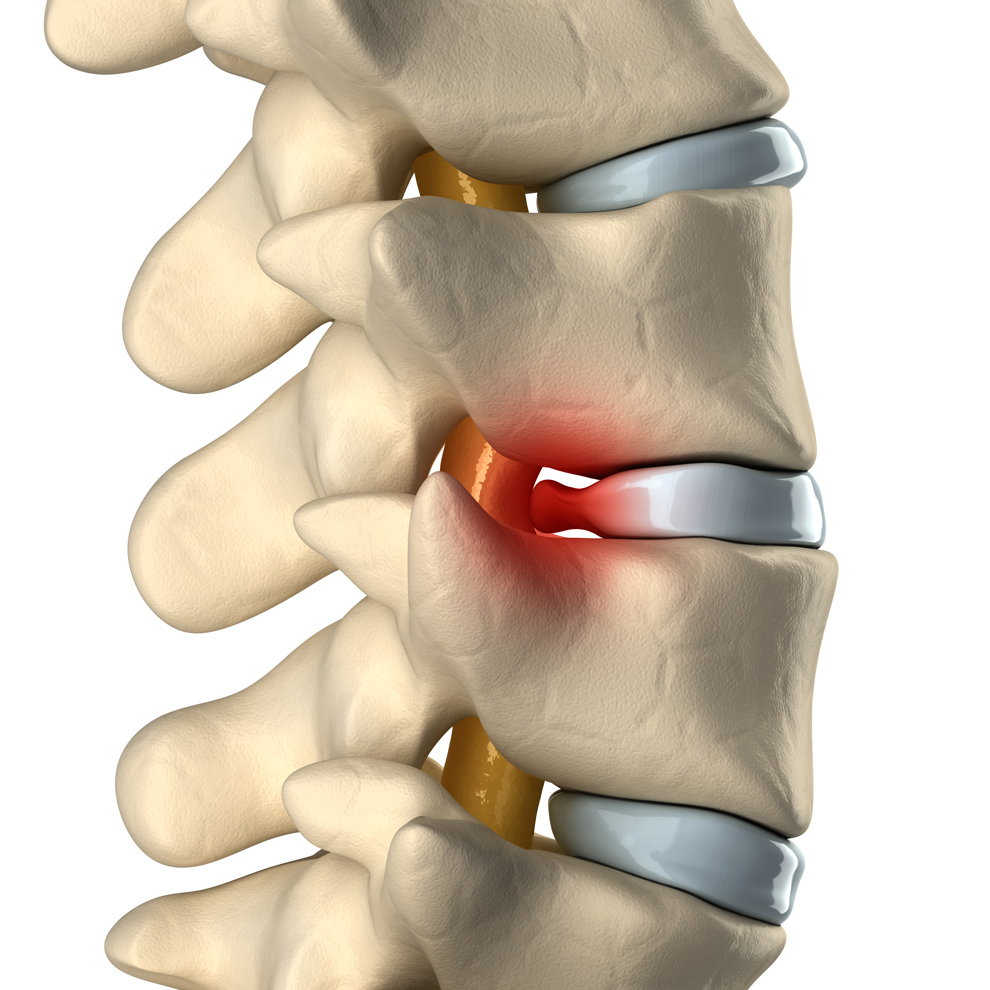

A slipped disc, also known as a herniated, bulging, or ruptured disc, occurs when one of the soft, gel-filled discs between the vertebrae in the spine shifts or ruptures, placing pressure on surrounding nerves. This condition can cause a range of symptoms, including pain, numbness, and muscle weakness. Slipped discs symptoms are common in the lower back (lumbar spine) and the neck (cervical spine) and can affect mobility, making even everyday tasks challenging.

The spine consists of vertebrae stacked on top of each other with intervertebral discs in between. These discs act as cushions and shock absorbers for the spine, helping to distribute loads and allowing flexibility in movement. Each disc has a tough, fibrous outer layer (annulus fibrosus) and a soft, gel-like core (nucleus pulposus). In a healthy spine, these discs absorb shock and reduce friction between vertebrae. When a disc herniates or slips, the soft core pushes through the damaged outer layer and exerts pressure on nearby nerves. For the best slipped disc treatment in Delhi NCR, consult with our expert Dr. Manoj Kumar who offers advanced treatment options to relieve pain and restore spinal health.